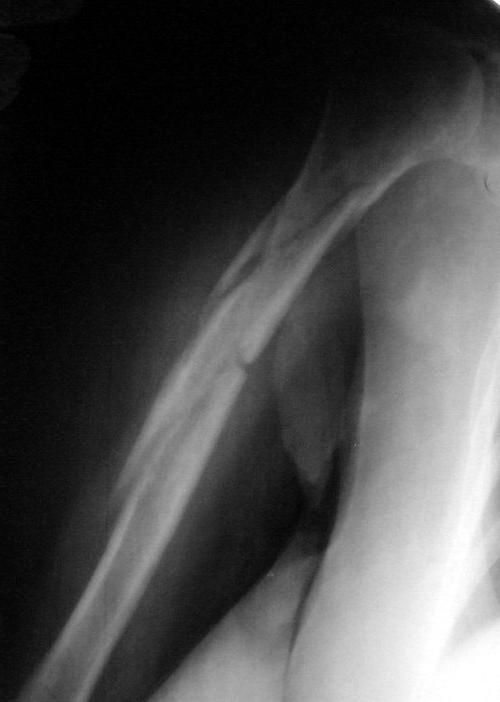

Многооскольчатый перелом плечевой кости в В/3 - ПРОДОЛЖЕНИЕ

Вот результат консервативного лечения данного перелома. Консолидация достаточная, клинически подвижности нет. Занимаюсь реабилитацией. Думаю функцию плечевого сустава можно будет восстановить на 70-80%